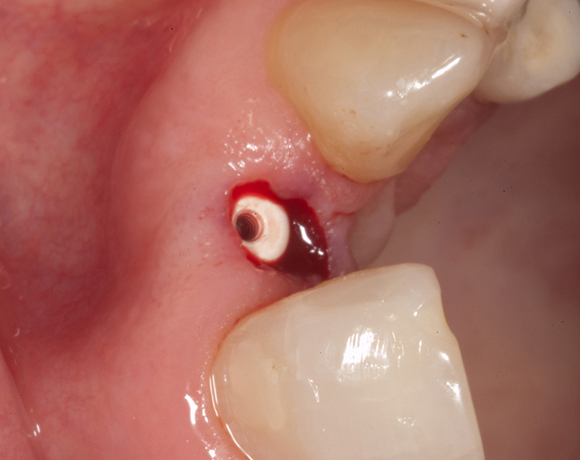

Zeramex T Implantat für Zahn 22

Ein Projekt aus dem Jahr 2013

Im vorliegenden Patientenfall musste der Zahn 22 nach erfolgloser Endodontie entfernt werden. Die Nachbarzähne waren kariesfrei, es wurde eine Marylandbrücke (eine Brücke mit zwei Flügelchen, die palatinal an den Nachbarzähnen verklebt werden) oder ein Implantat besprochen. Die Patientin hat sich für ein Vollkeramikimplantat entschieden. In der Diashow wird der operative Eingriff bis zur fertigen Krone gezeigt. Die Einheilzeit betrug drei Monate.